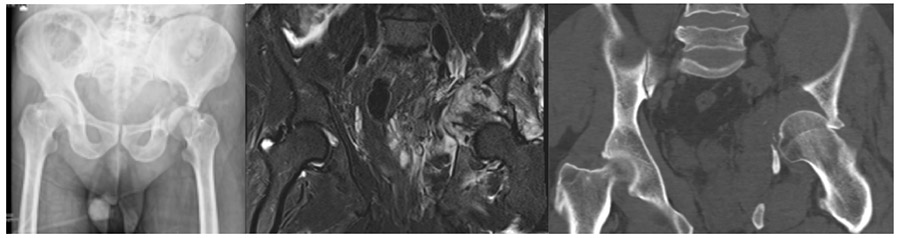

CASE 22: Thyroid cancer metastasized to the left hip bone (acetabulum), resulting in fractured dislocation.

Before the surgery: X-rays, MRIs, and CT scans show damage, a fracture, and a large tumor tissue in the left hip bone.